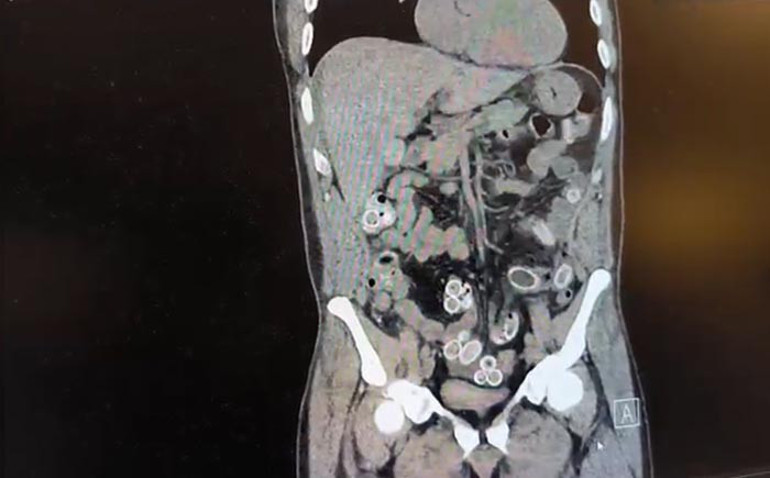

Beşiktaş’ta 3 bin kilometre uzaklıktaki Fas’tan uçakla Türkiye’ye gelen Cüneyt Ç. (52), 2 gün sonra mide ağrısı şikayetiyle hastaneye gitti. Tomografisi çekilen Cüneyt Ç.’nin mide ve bağırsaklarında yabancı madde bulunduğu tespit edildi.

Fas’tan yaklaşık 3 bin kilometre uzaklıktan uçakla Türkiye’ye gelen Cüneyt G., 2 gün sonra karın ağrısı şikayetiyle Fulya’daki özel bir hastaneye başvurdu. Yapılan muayenenin ardından Cüneyt G.’nin tomografisi çekildi. Şüphelinin mide ve bağırsaklarında yabancı madde tespit edilmesi üzerine hastane yetkilileri durumu polis ekiplerine bildirdi.

İhbar üzerine çalışma başlatan Beşiktaş Asayiş Büro Amirliği ekipleri, doktorlarla görüşme gerçekleştirdi. Doktorların değerlendirmesi sonrası ameliyata alınan Cüneyt Ç.’nin bağırsaklarından, toplam ağırlığı 259,7 gram olduğu öğrenilen 49 esrar macunu çıkarıldı. Şüpheliye ait 1 adet cep telefonu da hastane yetkilileri tarafından polis ekiplerine teslim edildi.